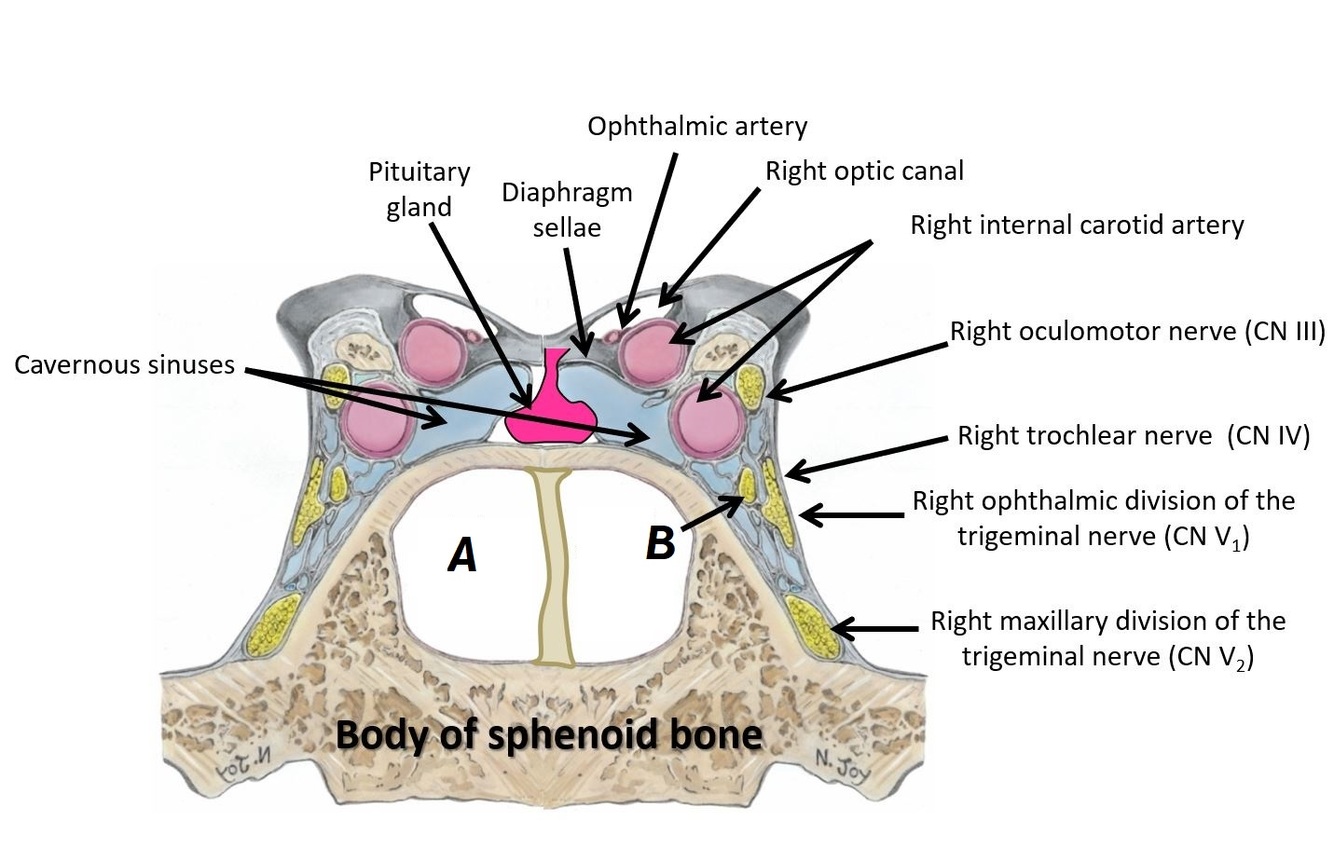

Name structures A and B

A - Left sphenoid sinus

B - Righ abducens nerve (CN VI)